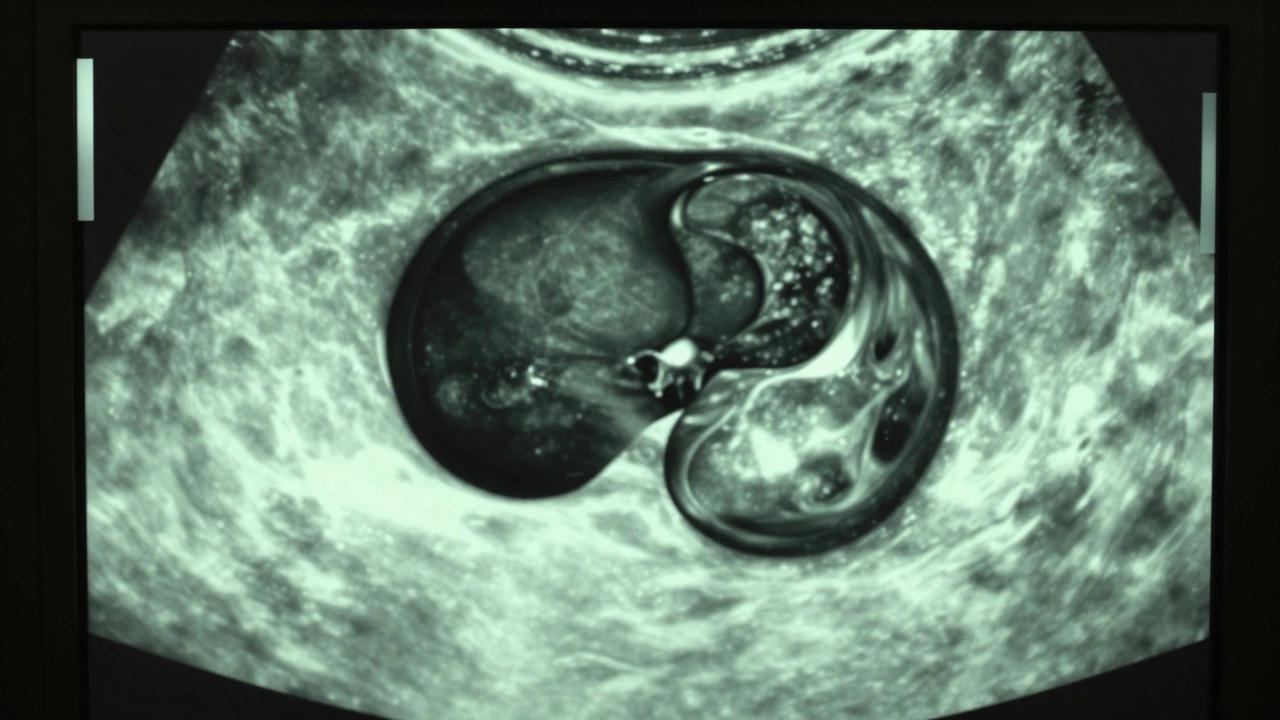

Сложные кисты выглядят иначе. Они могут иметь неровные границы, внутренние перегородки или эхогенные включения (светлые участки). Например, киста печени с кровоизлиянием внутри покажется темно-серой с вкраплениями светлых точек. Такие образования иногда содержат твердые компоненты или кровь, что делает их менее однородными.

Вот пример: киста почки с уплотненной стенкой. На УЗИ она выглядит как темное пятно, но с толстыми краями и небольшими светлыми пятнами внутри. Это может указывать на воспаление или другие изменения. Такие кисты требуют дополнительных исследований, например, КТ или МРТ, чтобы исключить серьезные заболевания.